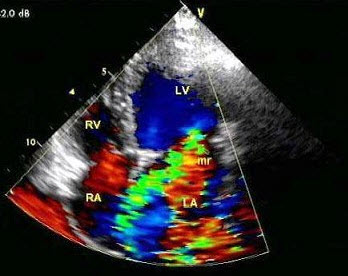

13、单项选择题

该病例最有可能诊断()

D.二尖瓣关闭不全

E.二尖瓣脱垂

14、单项选择题